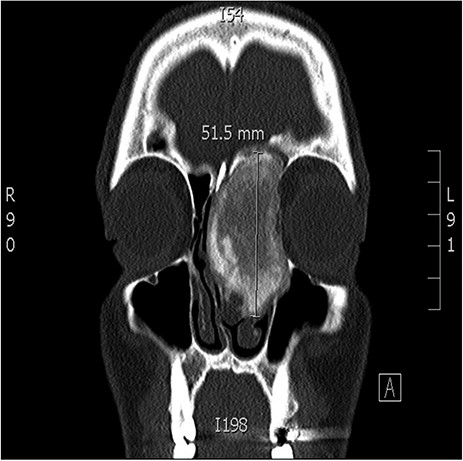

A 34-years-old man presented with left-sided facial pain, headache and nasal obstruction for a long duration, with no history of bleeding per nose, nor blurring of vision. Upon examination, there was a large left nasal cavity bony outgrowth pushing the middle turbinate and pushing the nasal septum to the right side (Fig. 1). CT scan of the paranasal sinuses showed a large mass centered in the left anterior ethmoid sinus, the mass measures 3.7 × 2.9 cm (trans-axial) (Fig. 2) and 3.7 × 5.2 cm (coronal) (Fig. 3), it has a heterogeneous density with calcified and soft-tissue component. The calcified component is in the periphery with central soft tissue density. The mass resulted in remodeling of adjacent bones with nasal septal deviation to the right, it extended superiorly to involve the frontal sinuses as well as invading the left cribriform plate and intracranial extension (Fig. 4), it extended inferiorly displacing the medial wall of the left maxillary antrum. The medial aspect of the mass caused remodeling of the medial wall of the left orbital cavity with bulging and displacement of the medial rectus muscle. The mass resulted in obstruction of the left frontal sinus.

Coronal CT image of the sinuses showing a large mass obstructing the frontal sinus.